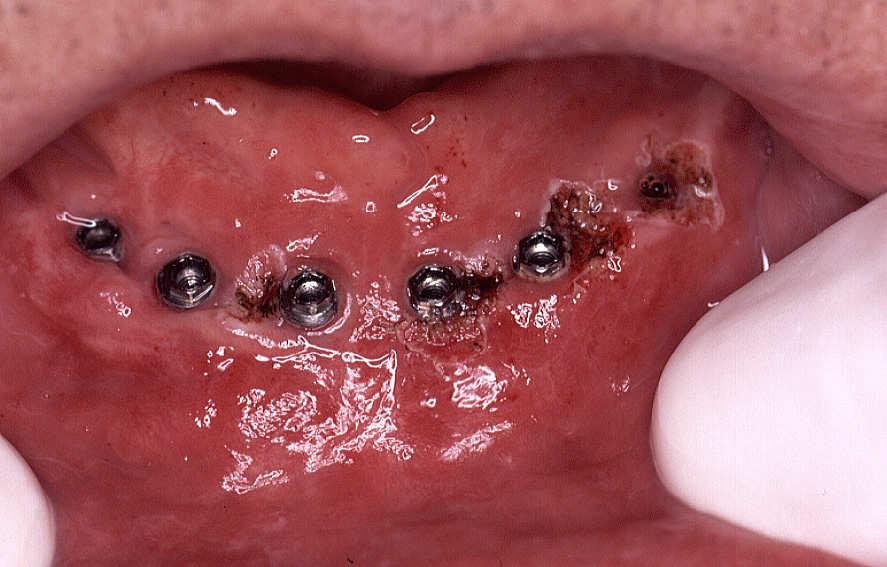

The treated zone after 14 days of the surgical intervention: very good cure and restoration of the gum around the implants.